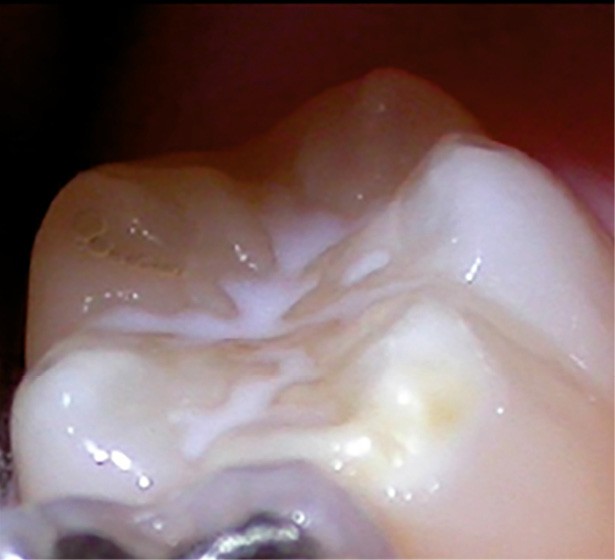

Cliniquement, les dents présentent des colorations blanches ou brunes opaques sur une partie ou sur toute la surface de la dent. Cette atteinte peut être légère (émail blanc, opaque), modérée (coloration jaune, brune, surface crayeuse et effondrement postéruptif de l’email) ou sévère (atteintes associées à des pertes de substances importantes) (fig. 1)

.